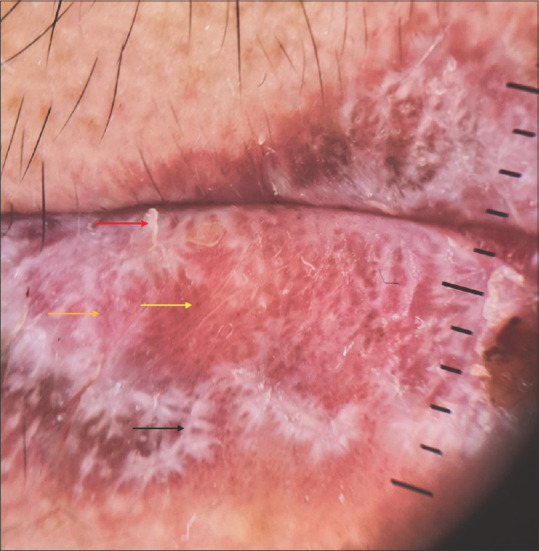

Figure 2.

Non-contact dermoscopy under polarised mode using DermLite DL4 (10X) showing leaf venation-like Wickham striae (black arrow), scaling (red arrow), dotted vessels (orange arrow), pigmented dots, and globules over a violaceous background (yellow arrow)